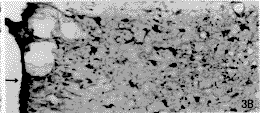

Nissl染色切片可见切口损伤的范围包括皮质、扣带和胼胝体等。术后14 d,损伤侧皮质的Nestin阳性反应最明显,涉及的范围较广。切口周围的Nestin免疫染色呈现一个梯度反应模式。离伤口越近处,反应越强烈,Nestin阳性细胞数越多;离伤口越远处,反应越弱,Nestin阳性细胞越少。皮质浅层的反应范围要比深层的大,冠状片上可观察到一个Nestin阳性的楔形反应区(图1A,见插页1)。而从前后的连续切片来看,随着逐渐远离伤口,Nestin阳性细胞的消失也逐渐是从皮质深层过渡到浅层(图1B,图1C)。在最靠近伤口的区域,Nestin阳性细胞密集,胞体肥大,多呈星形,突起粗大而长,互相交织成网,环绕着伤口的周边。离伤口稍远的部位,Nestin阳性细胞密度降低,胞体较小,突起较细而短(图2A)。非损伤侧的皮质未观察到Nestin的表达。GFAP免疫染色显示在伤口的周围出现许多胞体较大的星形阳性细胞,其出现的模式与Nestin阳性细胞的反应模式相似。但其涉及的范围、阳性细胞密度、胞体和突起的大小均小于Nestin阳性细胞(图2B)。术后30 d,皮质内切口周围仍存在大量的Nestin阳性细胞,但阳性细胞的排列较14 d的整齐(图3A)。而GFAP阳性的肥大细胞数目及其突起数目均较14 d的少(图3B)。

图3 损伤后30 d大脑皮质的Nestin和阳性细胞(A)和GFAP阳性细胞(B)。箭头所指为皮质的表面。x200

, http://www.100md.com Flg.3 The Nestin positive cells(A)and GFAP opsitive cells(B)in the cortex im the 30 day after injury.The arrow indicates the surfacd of the cortex.×200